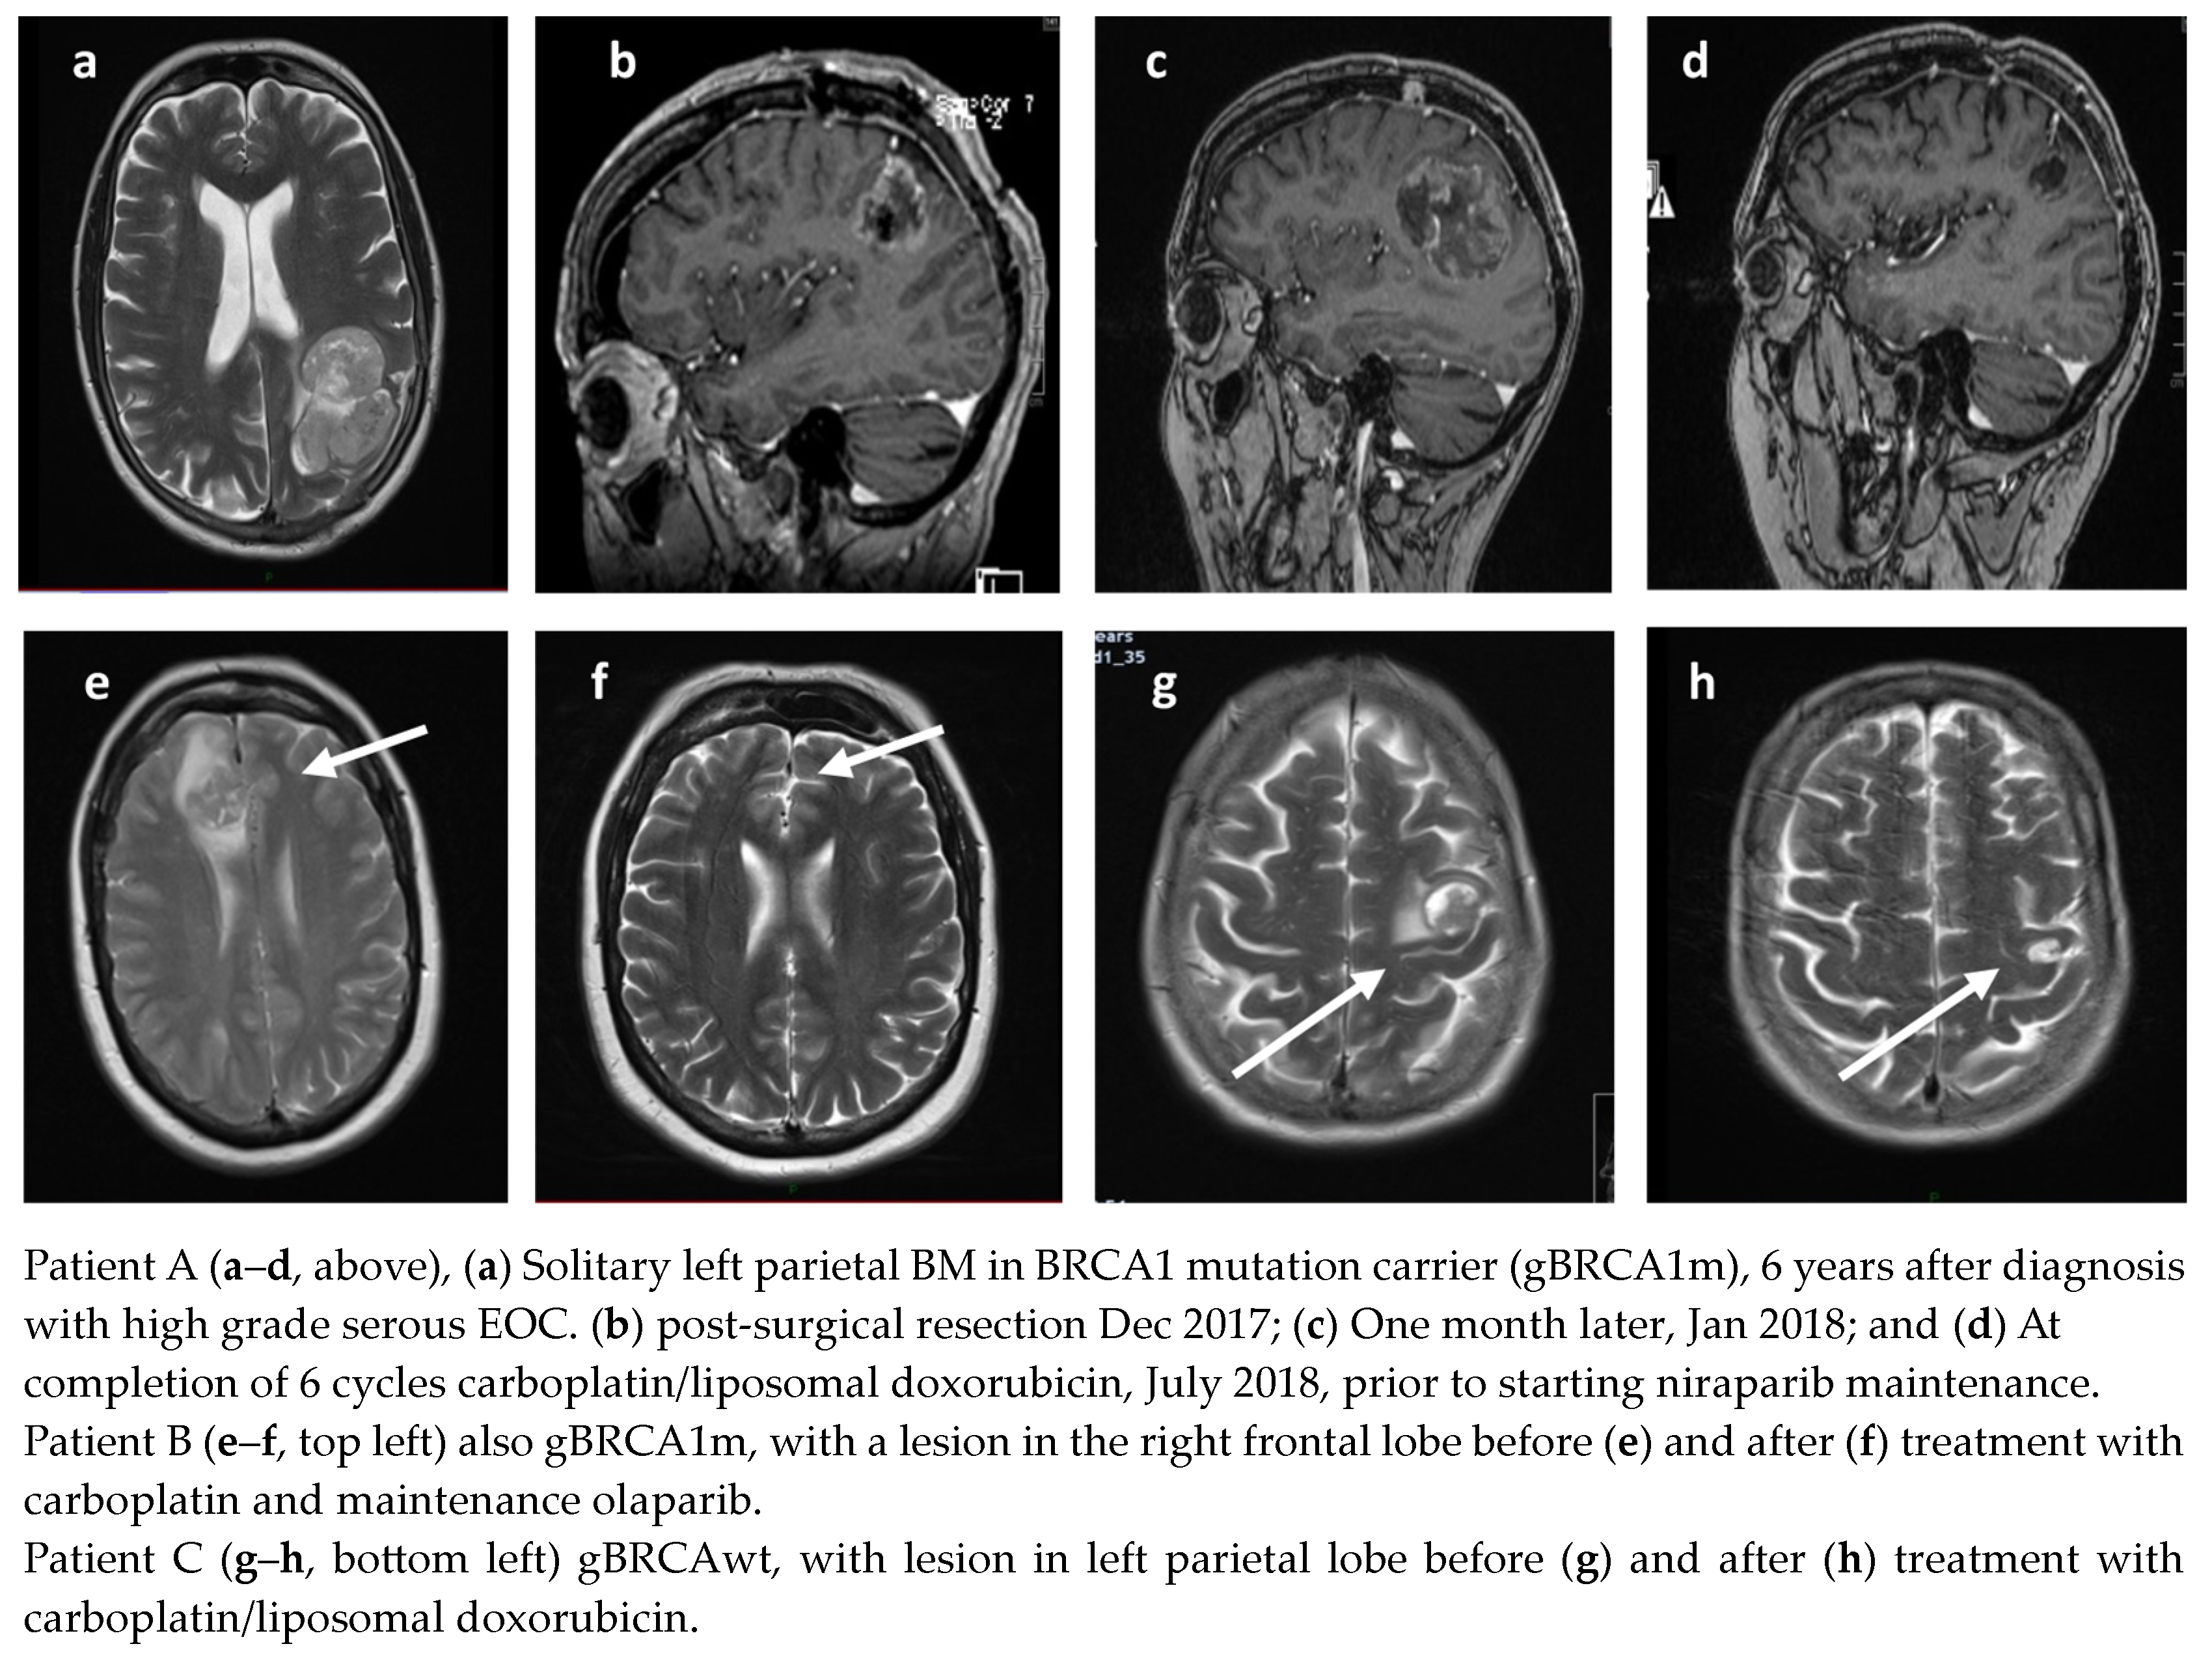

A total of 35 patients received treatment for BM. The median time to BM from the end of first-line treatment for BRCAm patients was 21.5 months (range 8–42), and 23 months (range 16–27) for BRCAwt patients. BM as the only site of first relapse occurred in 14 patients (BRCAm n = 7 and BRCAwt n = 7). Thirteen of these patients had an initial remission of greater than 1 year (13–52 m) prior to their relapse with BM. Systemic treatments were not planned for five of these fourteen BM patients, although one patient responded well to chemotherapy having progressed within six weeks of surgery (Figure 1). A total of 7/14 patients (three BRCAm) had further relapse(s) following treatment, with a median PFS of 13.5 months (2–25 months). At the time of analysis, 6/14 (four BRCAm) remain in remission, with a median PFS of 37 months (10–64 months), following treatment for BM. Four remain on PARPi. Examples of patients are demonstrated in Figure 2a–h.

Figure 2.

Radiological responses of three patients with BM on PARPi therapy (arrows denote sites of brain metastases).

Patient A, with gBRCA1m, was diagnosed with a solitary BM 42 m after initial diagnosis (Figure 2a). The left parietal lobe mass was surgically resected (Figure 2b), but she presented one month later with deteriorating neurology; her performance status had declined to three. Repeat MRI demonstrated early recurrence in the surgical bed and a new right parietal metastasis (Figure 2c). She was treated with six cycles of carboplatin/liposomal doxorubicin followed by maintenance niraparib; she remains in complete remission (CR) over 36 months later and is still taking niraparib (Figure 2d). Patient B, also gBRCA1m, was treated with carboplatin and maintenance olaparib (Figure 2e,f). Patient C, gBRCAwt, received caboplatin/liposomal doxorubicin and maintenance niraparib (Figure 2g,h).